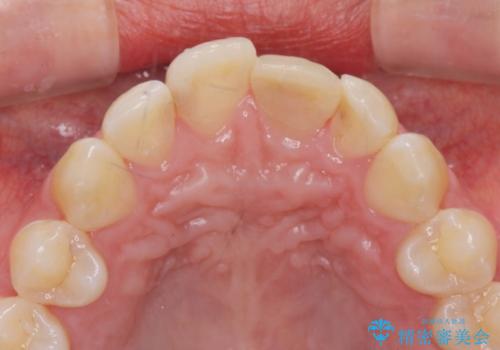

前歯の変色を改善するセラミッククラウン治療

- 以前に前歯を強打し、変色してきた前歯の審美性の改善を希望されて来院されました。

X線検査の結果、変色をきたしている歯は根尖病変が存在し、神経が失活している状態でした。

根管治療を行ったのち、セラミッククラウンで審美性を改善していきます。

歯科技工士との綿密な打ち合わせで、非常に自然なセラミッククラウンを作製することができました。